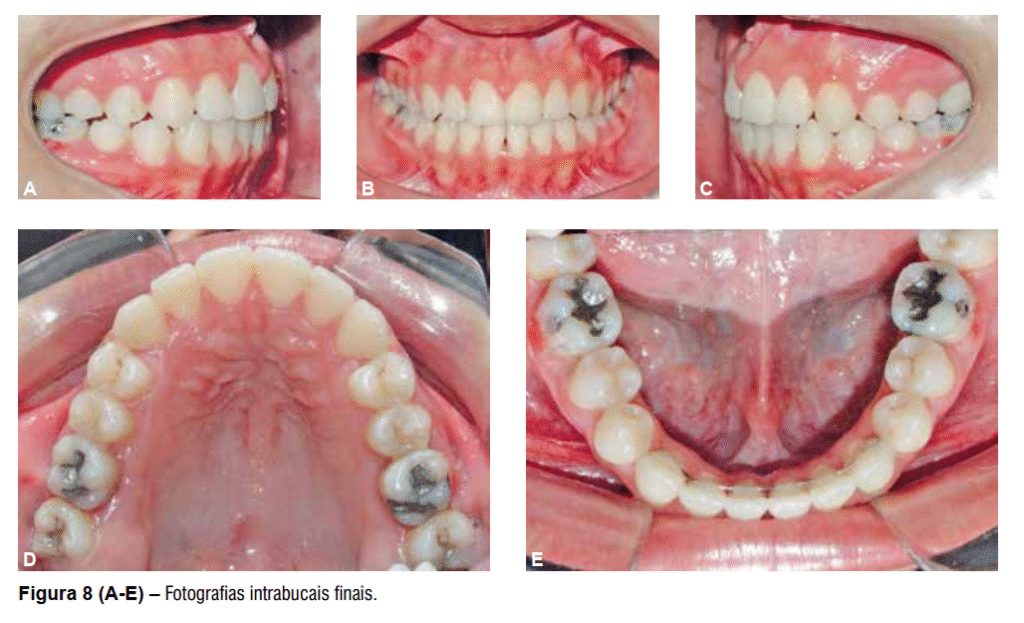

Após a remoção do aparelho fixo foi instalada como contenção uma placa de Hawley superior, 3×3 inferior e uso noturno de mentoneira com finalidade de restringir o crescimento mandibular. O tratamento proposto possibilitou a correção da discrepância transversal e da relação anteroposterior de forma satisfatória, melhorando o perímetro do arco e obtendo-se uma relação molar de Classe I (Figura 8 A-E), além da melhora significativa do perfil facial e estética mais agradável (Figura 9 A-B). As telerradiografias inicial e final mostram a melhora da relação entre as bases ósseas (Figura 10) juntamente com a sobreposição dos cefalogramas (Figura 11).

O componente dentoalveolar da maxila apresentou maiores alterações, assim como já era esperado. Os incisivos superiores apresentaram vestibularização e protrusão enquanto os molares superiores apresentaram mesialização com angulação da sua coroa para a mesial (Tabela 1). O componente dentoalveolar inferior apresentou suaves alterações, principalmente em relação à extrusão sofrida pelos incisivos inferiores (Tabela 1).

Na relação entre os dentes superiores e inferiores houve grande melhora representada pelas variáveis:

relação molar, trespasse horizontal e trespasse vertical (Tabela 1), assim como houve visível melhora em relação ao perfil facial, que ao final do tratamento se apresentava menos côncavo (Tabela 1)